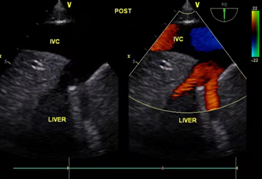

手术前后B超对比

12月4日,手术当日,妇产科陈必良教授、马佳佳医生开腹,游离出巨大的子宫肌瘤及双侧附件,切除后分离出瘤体远端,游离下腔静脉。心血管外科董小超副教授开胸在心脏不停跳并行体外循环下切开右房,探查右房内瘤体情况,通过腹部切口,将髂静脉切开分离肿瘤,于肿瘤起始部位切断肿瘤,自右心房内取出瘤体。循环稳定,术中食道超声持续观察以确定心内瘤体彻底取出。患者病变子宫极大,瘤体呈圆柱形,长约30-40cm。术后患者转入心血管外科监护室继续监护治疗。术后当天,患者恢复自主呼吸,生命体征平稳,顺利拔管。病情稳定后安返病房,与家人团聚。